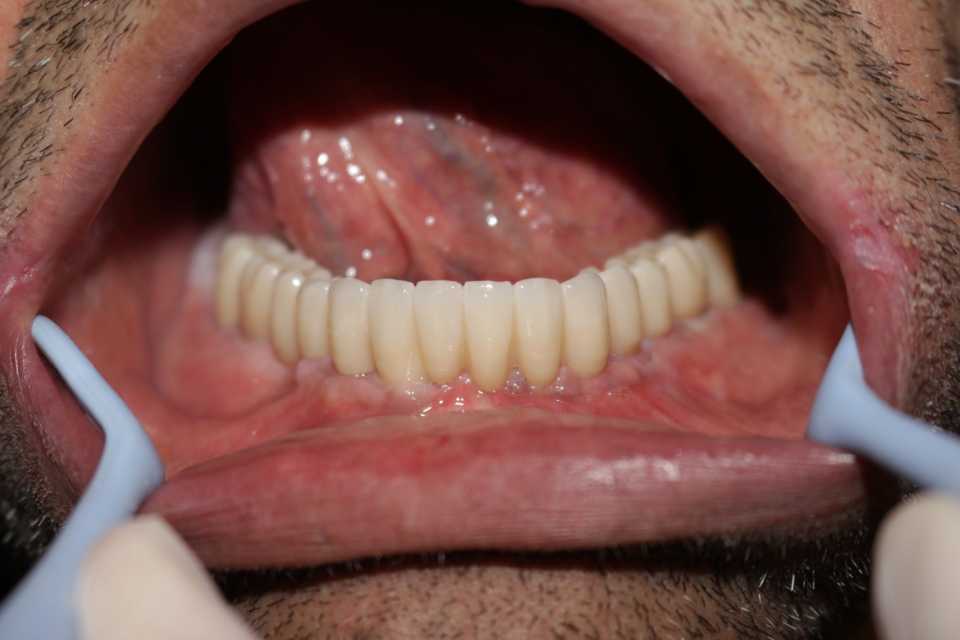

Pacientul Nicu D., în vârstă de 50 de ani, s-a prezentat în cabinet cu o edentație totală mandibulară în urma unei boli parodontale.

Împreună cu pacientul am hotărât realizarea unei lucrări protetice fixe inșurubabile pe 6 implanturi (implanturi Paltop). Lucrarea a fost realizată din ceramică pe zirconiu.

Implantul Paltop oferă posibilitatea realizării unor lucrări cu o estetică impecabilă și o afectare minimă a țesuturilor la locul implantării. Profilul concav al bontului protetic ajută la formarea unui țesut gingival dens la nivelul legăturii transgingivale scăzând vizibilitatea bontului.